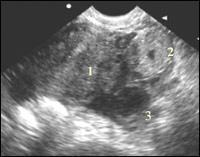

| Рисунок 1

| Эхографические признаки внематочной беременности Эктопически расположенное плодное яйцо с живым эмбрионом (в 5-10%) (развивающаяся беременность)

Диагностика достоверного признака развивающейся эктопической беременности основывается на обнаружении за пределами полости матки плодного яйца с эмбрионом, у которого имеются признаки жизнедеятельности: кардиальная пульсация, двигательная активность. Учитывая, что свыше 90 % случаев занимает трубная беременность, то для выявления обследуют область в проекции придатков, те есть от трубных углов тела матки, по ее заднебоковым поверхностям, к боковым стенкам малого таза и позадиматочное пространство. Таким образом, будут исследованы зоны возможной локализации трубной беременности интерстициального, перешеечного, ампулярного отделов, а также такие редкие места расположения как беременность в рудиментарном роге и интралигатурная.

Обнаружение патологического образования в проекции придатков является наиболее точным из всех косвенных признаков. Данное образование представляет собой трубу с плодовместилещем. В тех случаях, когда имеется прогрессирующая трубная беременность малого срока, в просвете маточной трубы определяется полость амниона округло-овальной формы, внутри которой можно визуализировать желточный мешок в виде кольцевидной структуры. Особенностью визуализации плодного яйца в маточной трубе является хорошо определяемый хорион, который окружает полость амниона по периферии в виде ткани солидной структуры. Такая отчетливая визуализация хориона объясняется разной эхогенностью тканей. Если в полости матки трофобласт и эндометрий имеют одинаковые эхографические характеристики, то в просвете трубы, где слизистая очень тонкая, хорион хорошо определяется как зона повышенной эхогенности на гипоэхогенном фоне мышечного слоя стенки. Дополнительным эхогрфическим признаком является отсутствие связи выявленного образования с маткой и яичником, для чего помогает исследование имитации двуручного исследования. Применять этот прием следует очень осторожно, помня, что при форсированных движениях возможен разрыв трубы. Более щадящим методом, однако, менее надежным является глубокий вдох и выдох пациенткой, при котором происходит смещение внутренних органов.